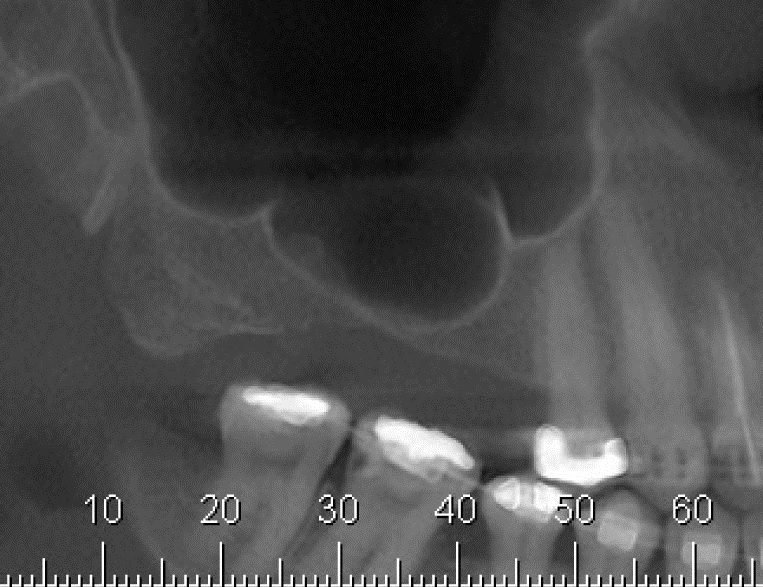

Enxerto de seio maxilar